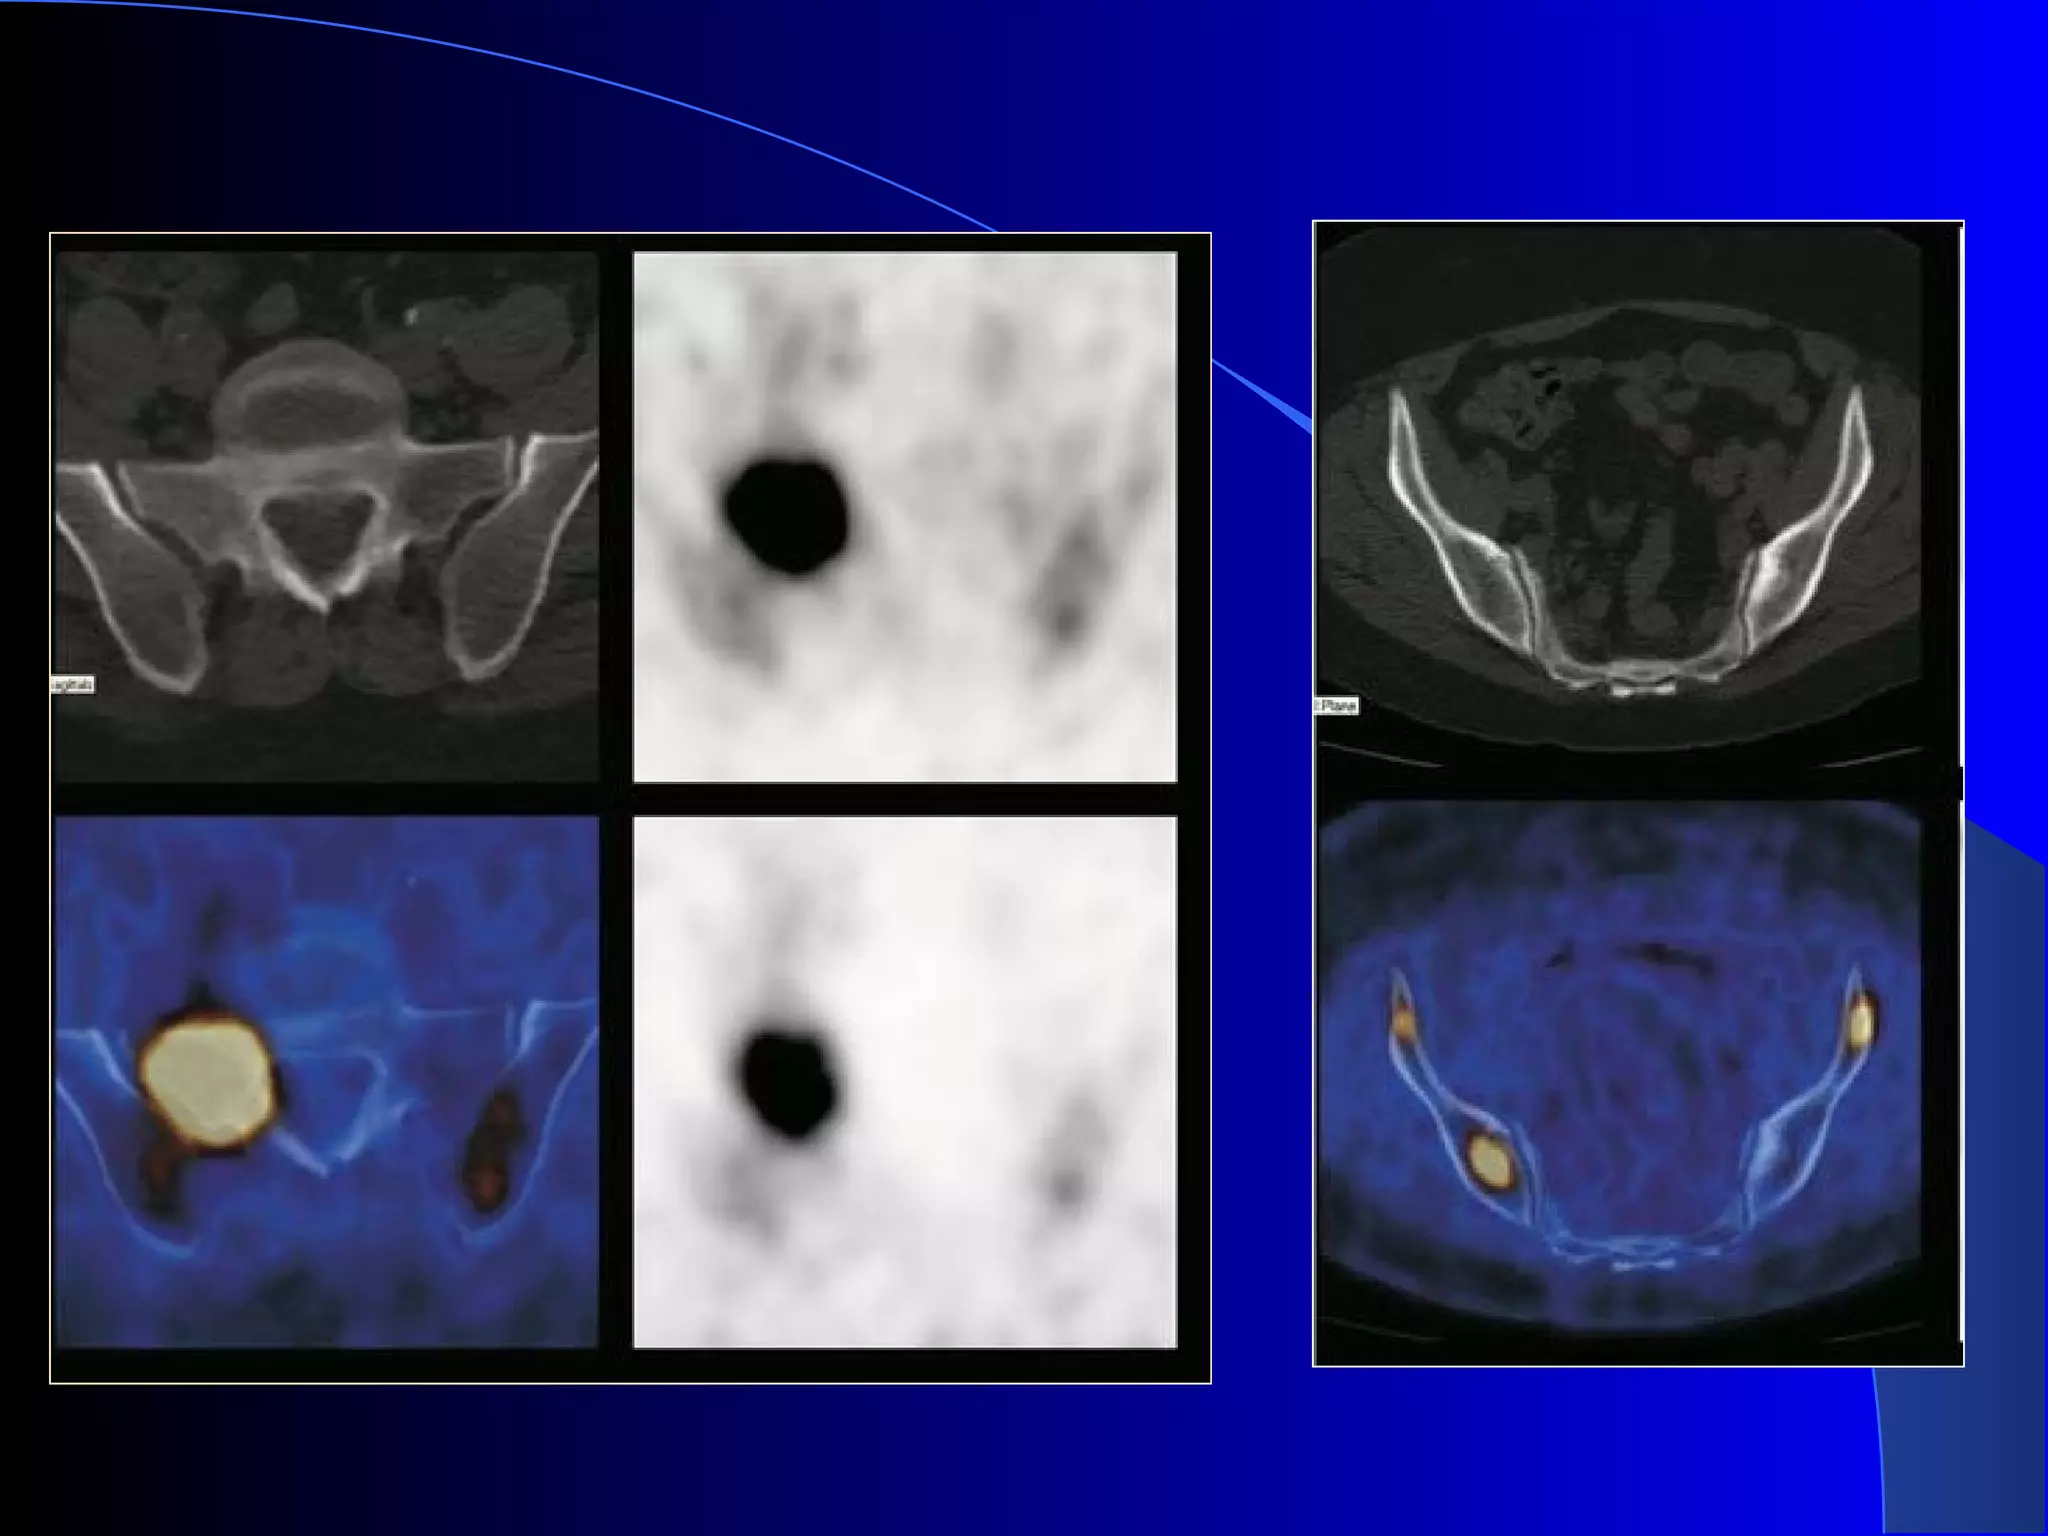

Focal FDG accumulation in the ureters is a

common finding dueto the pooling of radiotracer

in the recumbent patient.

althoughthe intensity and location of uptake

usually allow accurateidentification of the ureters

in patients with abdominal malignancies, this

finding can be misdiagnosed as pelvic lymph

node metastasisor nodal lymphoma.